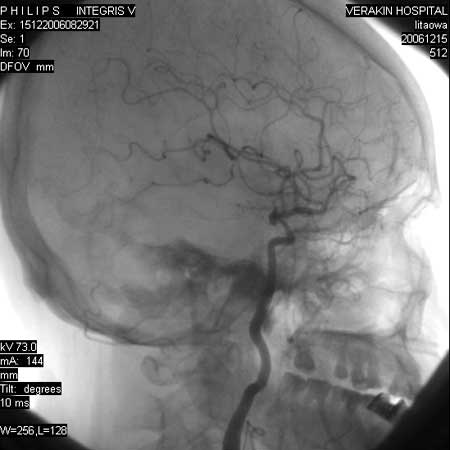

标题: DSA0063:颈内动脉血管造影

女,60岁,行全脑血管造影,图片较多,选了左颈内动脉造影100幅图中的10幅图片,请包涵。

实际上是左颈总动脉造影

更正:今天才看到本例脑血管造影全部过程,实际上仍是单侧的颈内动脉造影,只是在造影过程中,导管头位置平c4水平,刚好越过颈外动脉,本帖图片中颈外动脉显影系高压注射时造影剂部分返流到颈外动脉所致,特此更正!

另外:大家讨论的\"动脉瘤\"实际是血管分支重叠影像,本帖单侧颈内动脉仅见轻度动脉硬化性狭窄..参考旋转dsa请连接:http://www.sdhct.com.cn/radinet/read.php?tid=19818